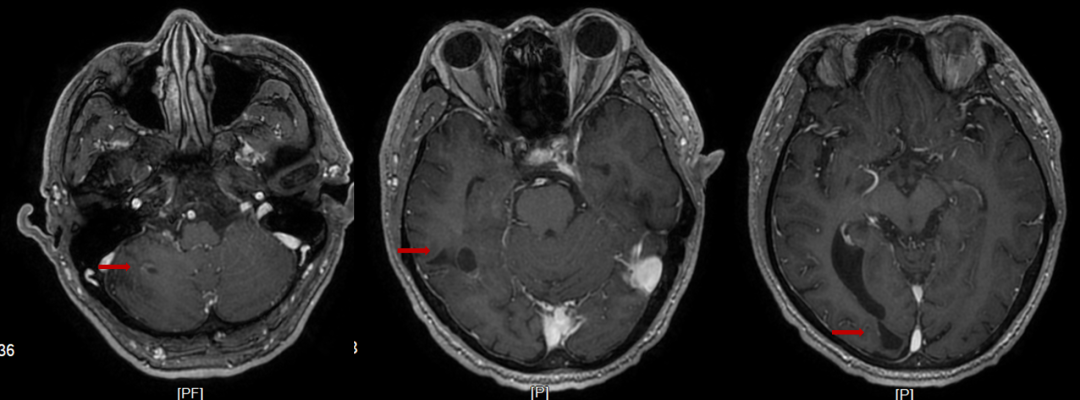

2022-08-04颅脑MRI:右侧小脑半球、右侧额颞顶枕叶及左侧放射冠区异常密度影,考虑多发占位性病变。

图1.首诊颅脑MRI